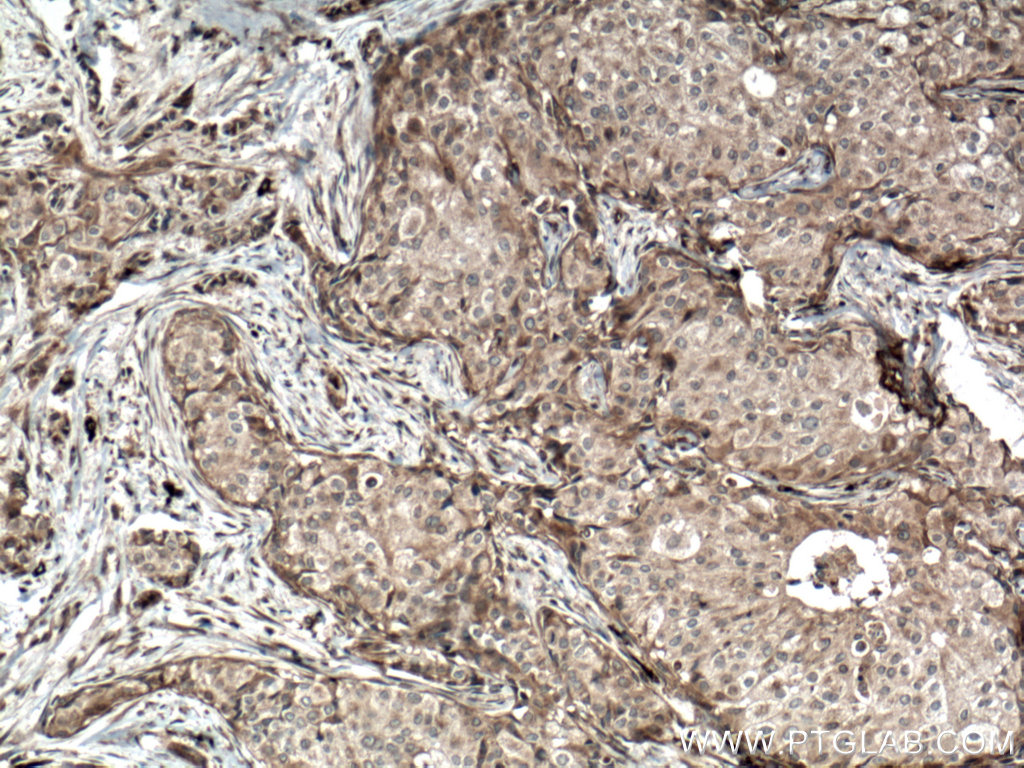

| Positive IHC detected in | human cervical cancer tissue, human breast hyperplasia tissue, human breast cancer tissue Note: suggested antigen retrieval with TE buffer pH 9.0; (*) Alternatively, antigen retrieval may be performed with citrate buffer pH 6.0 |

| Immunohistochemistry (IHC) | IHC : 1:750-1:3000 |